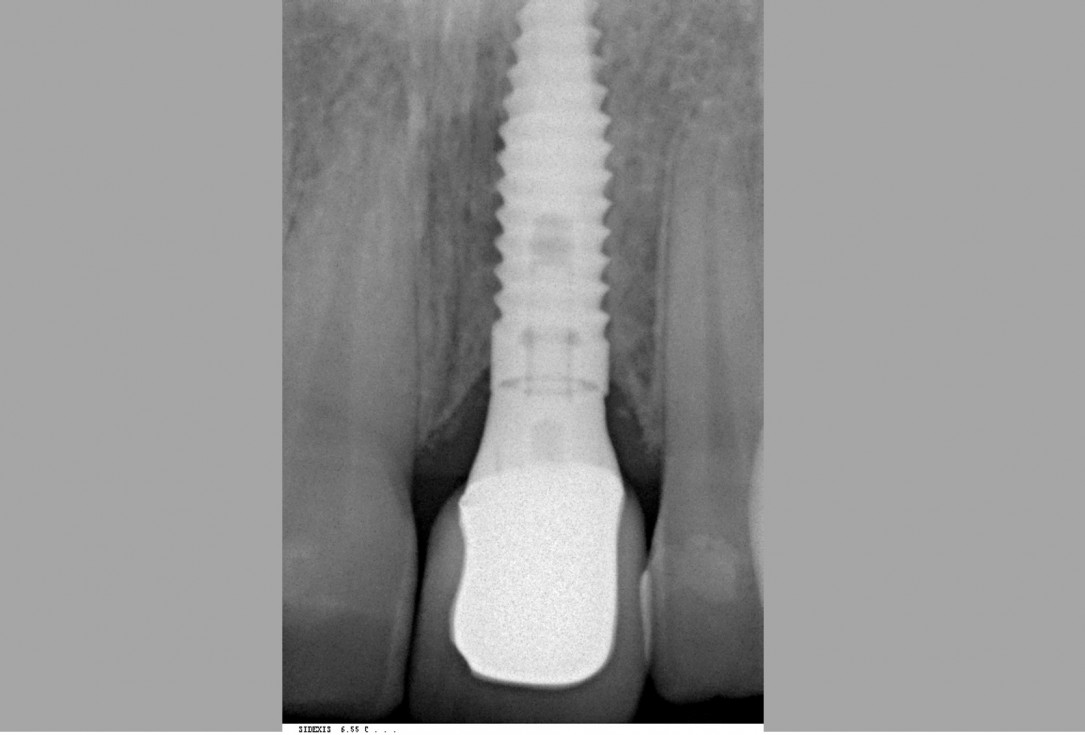

12/12 - Radiographic control five years post-operativeTreatment of dehiscence defect with cerabone® & Jason® membrane - Dr. M. Steigmann